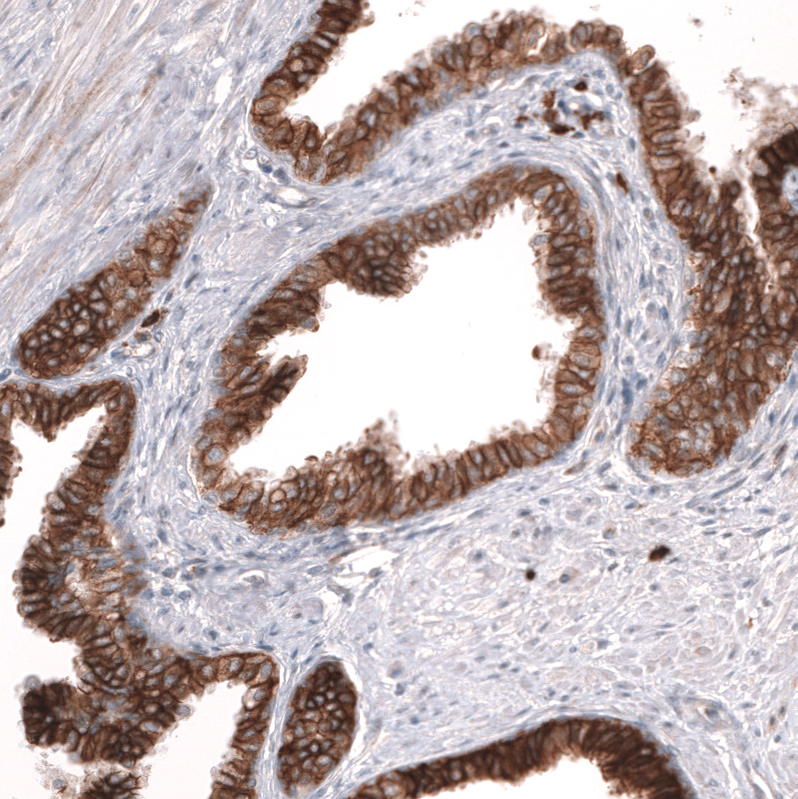

Immunohistochemistry analysis in human prostate and skeletal muscle tissues using AMAb91898 antibody. Corresponding ADAM10 RNA-seq data are presented for the same tissues.